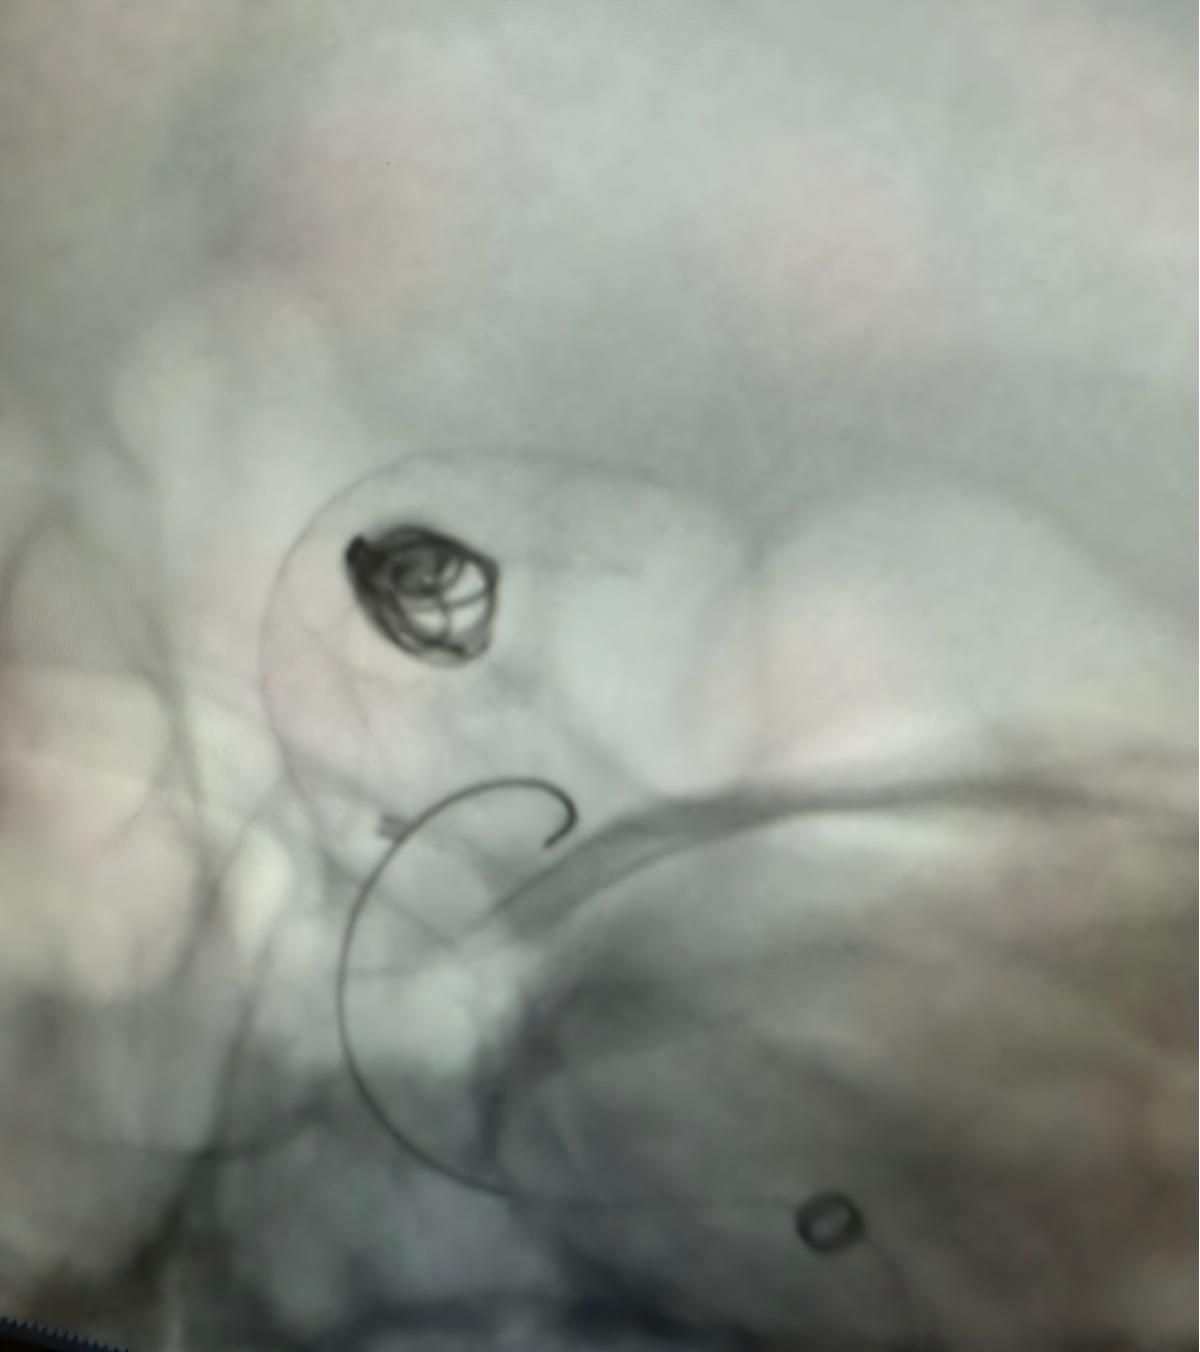

Le traitement a utilisé le Nuva®Déverseur d'écoulement (TJED-D 5.0-14), Perdenser®Bobine 3D, et Frepass®Microcathéter (TJMC18 Plus) pour un anévrisme de l'artère communicante postérieure.